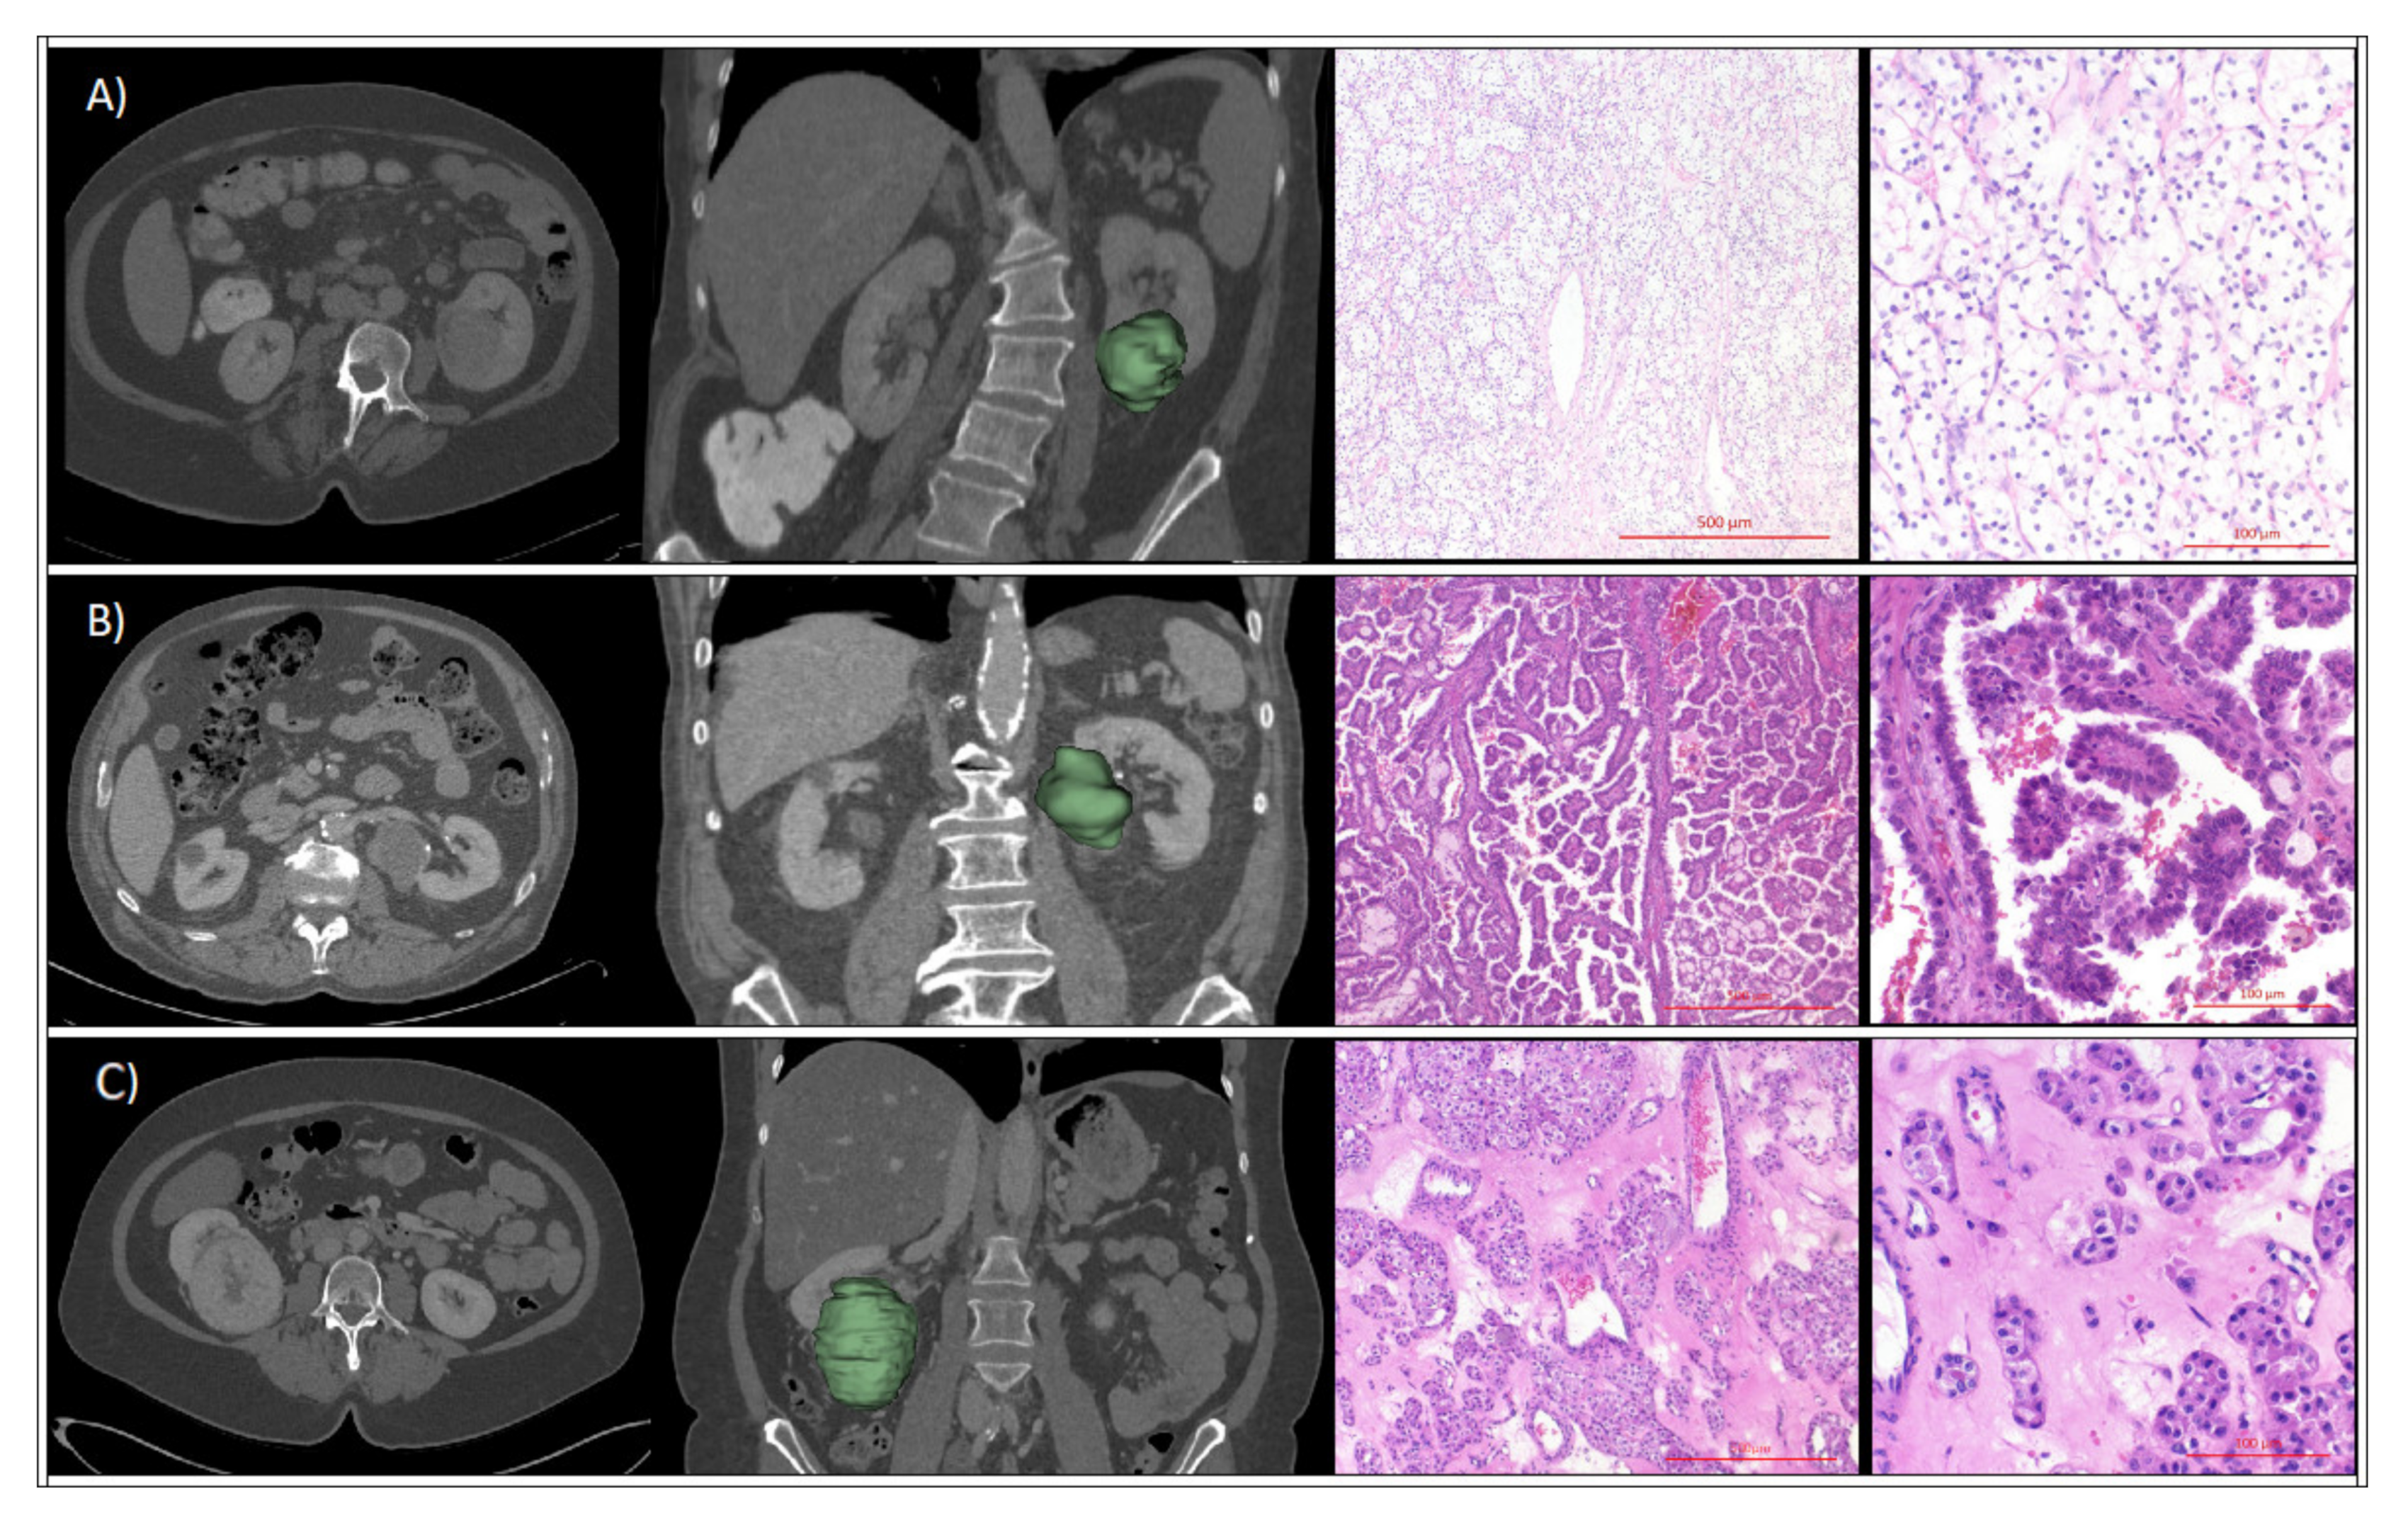

4.2. CT Imaging

4.3. Radiomic Feature Analyses

4.4. Renal Tumor Assessment